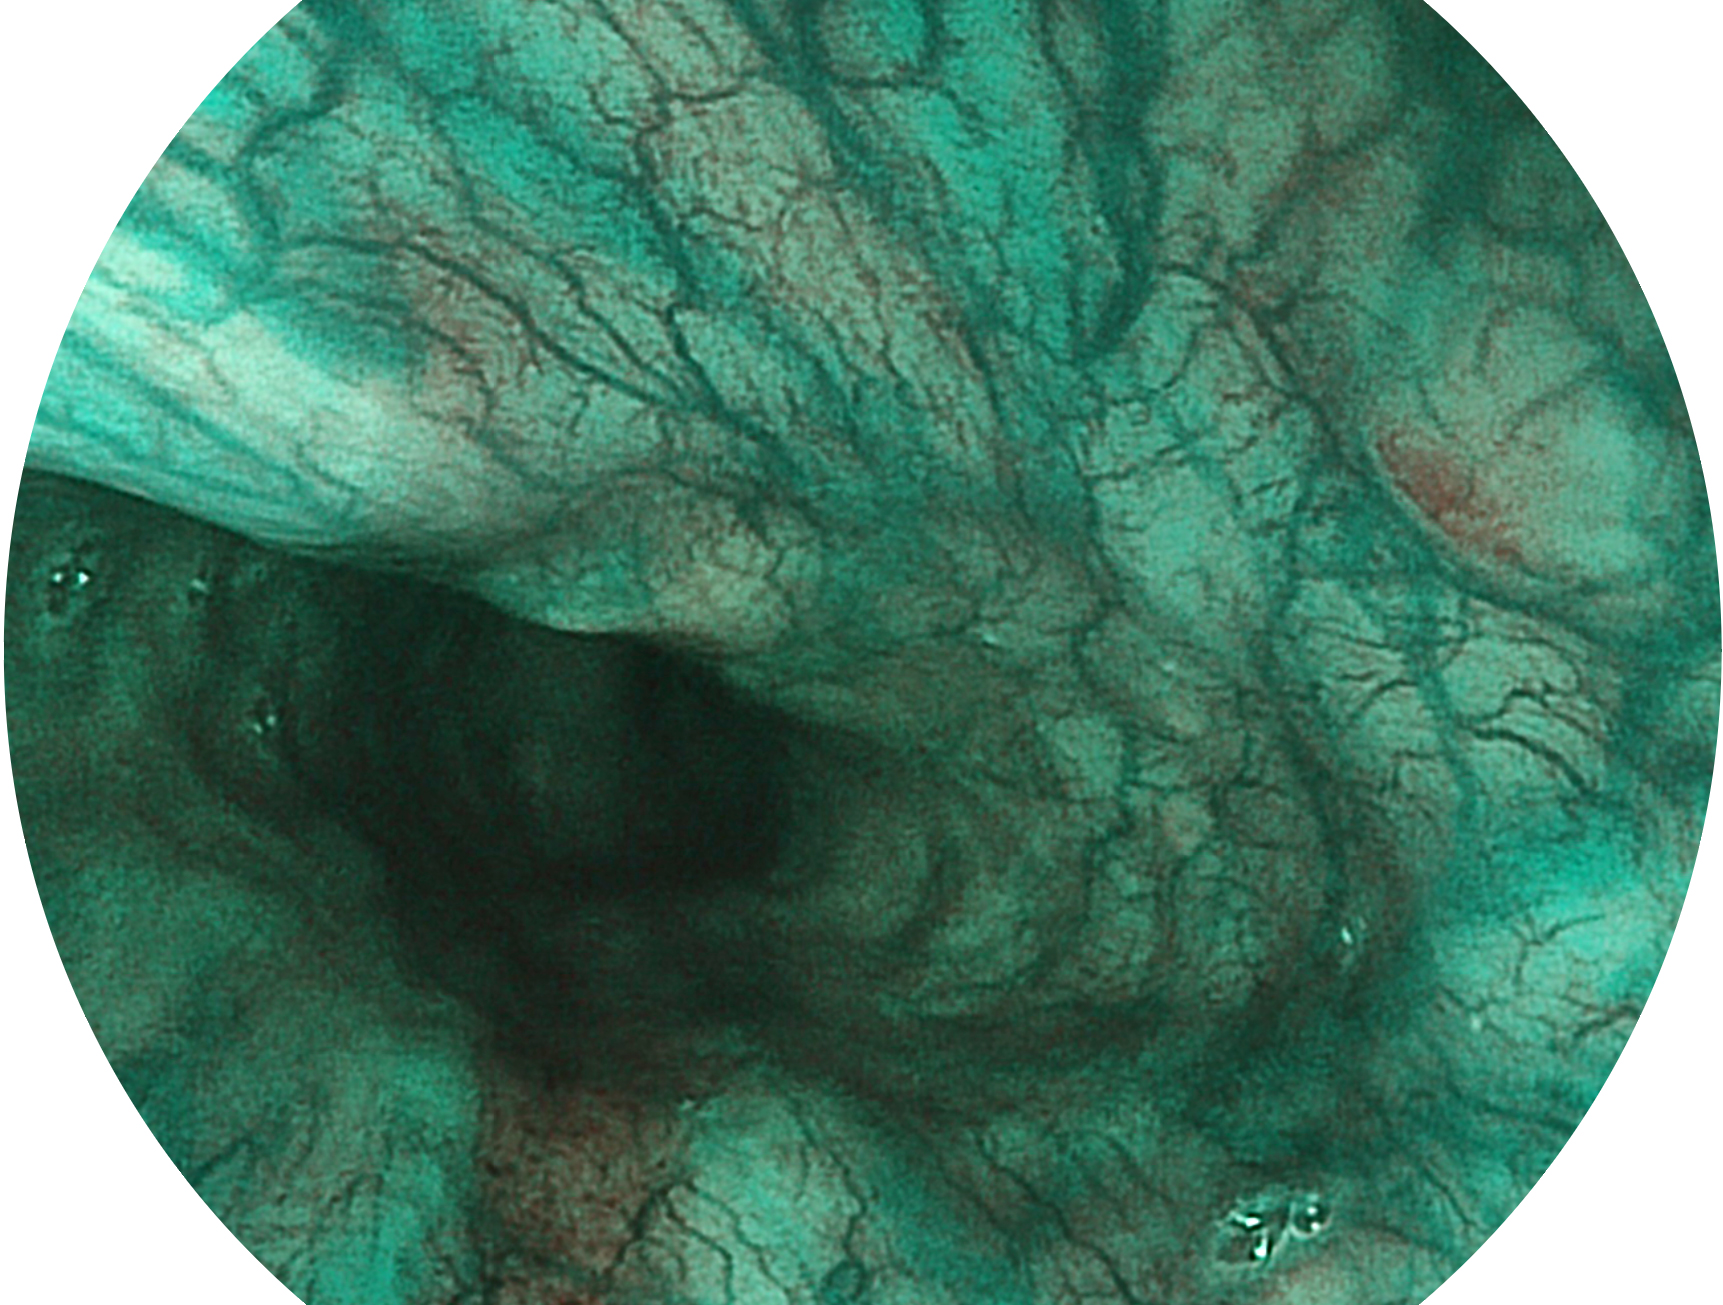

诸侯快讯官网新开发的内镜染色技术,主要是基于多波长LED 光源的开发,VLS-55Q 四波长LED 光源是由四个不同颜色的LED光按照相应照明模式所规定的特定发光比例进行合束后形成,合束后形成的照明光的光谱由红光、绿光、蓝光及蓝紫光这四个不同的波段范围构成。具有更高光谱自由度,通过光谱比例的控制,实现了聚谱成像技术,英文全称为“Spectral Focused Imaging, SFI”,缩写为“SFI”和光电复合染色成像技术,英文全称为“Versatile Intelligent Staining Technology, VIST”,缩写为“VIST”。